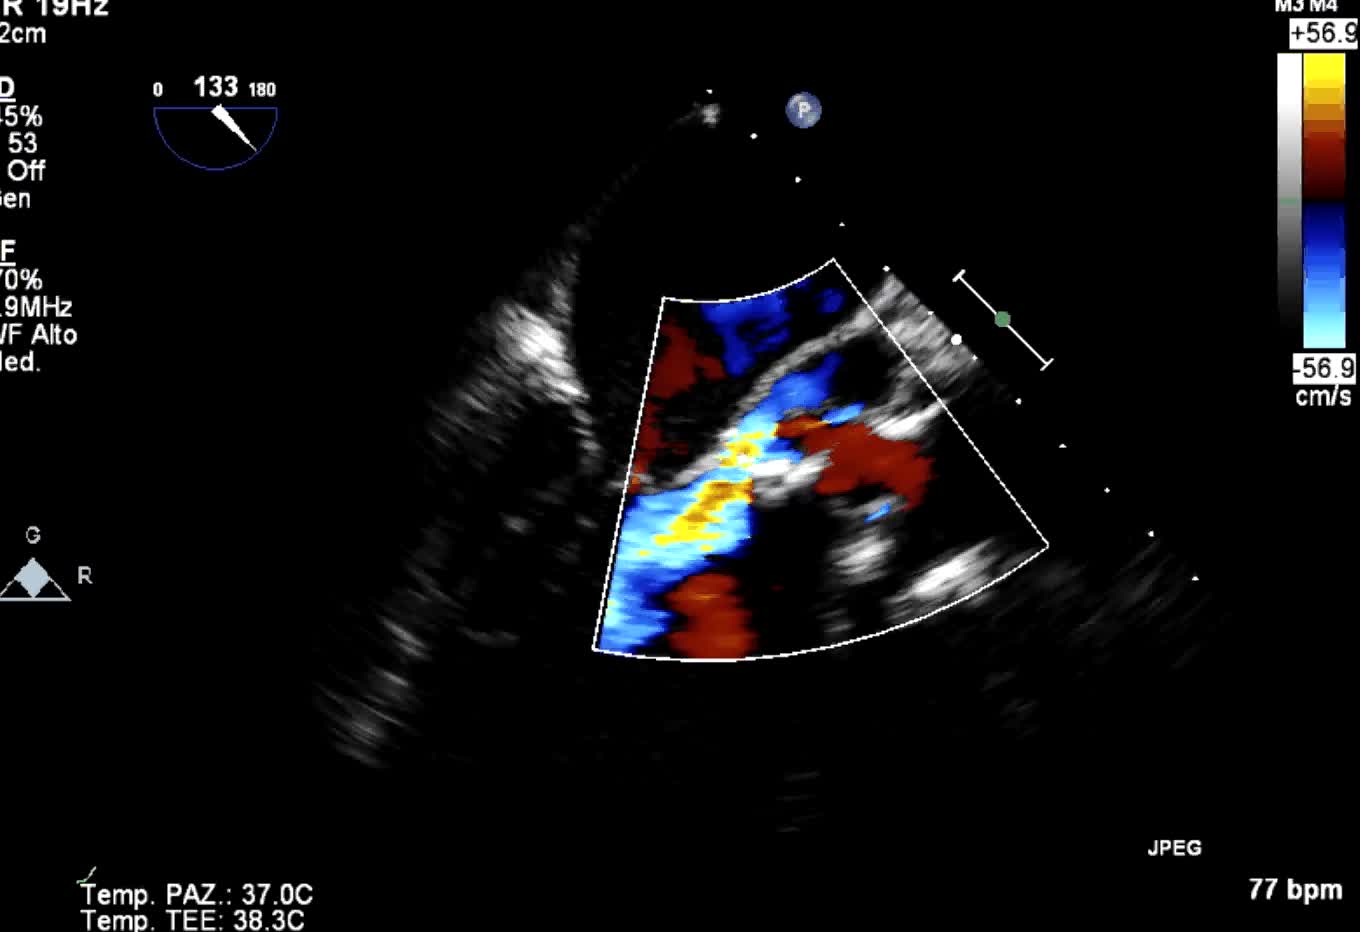

Distacco di protesi meccanica mitralica da endocardite infettiva

Autore:

Manfredo Cerchiello